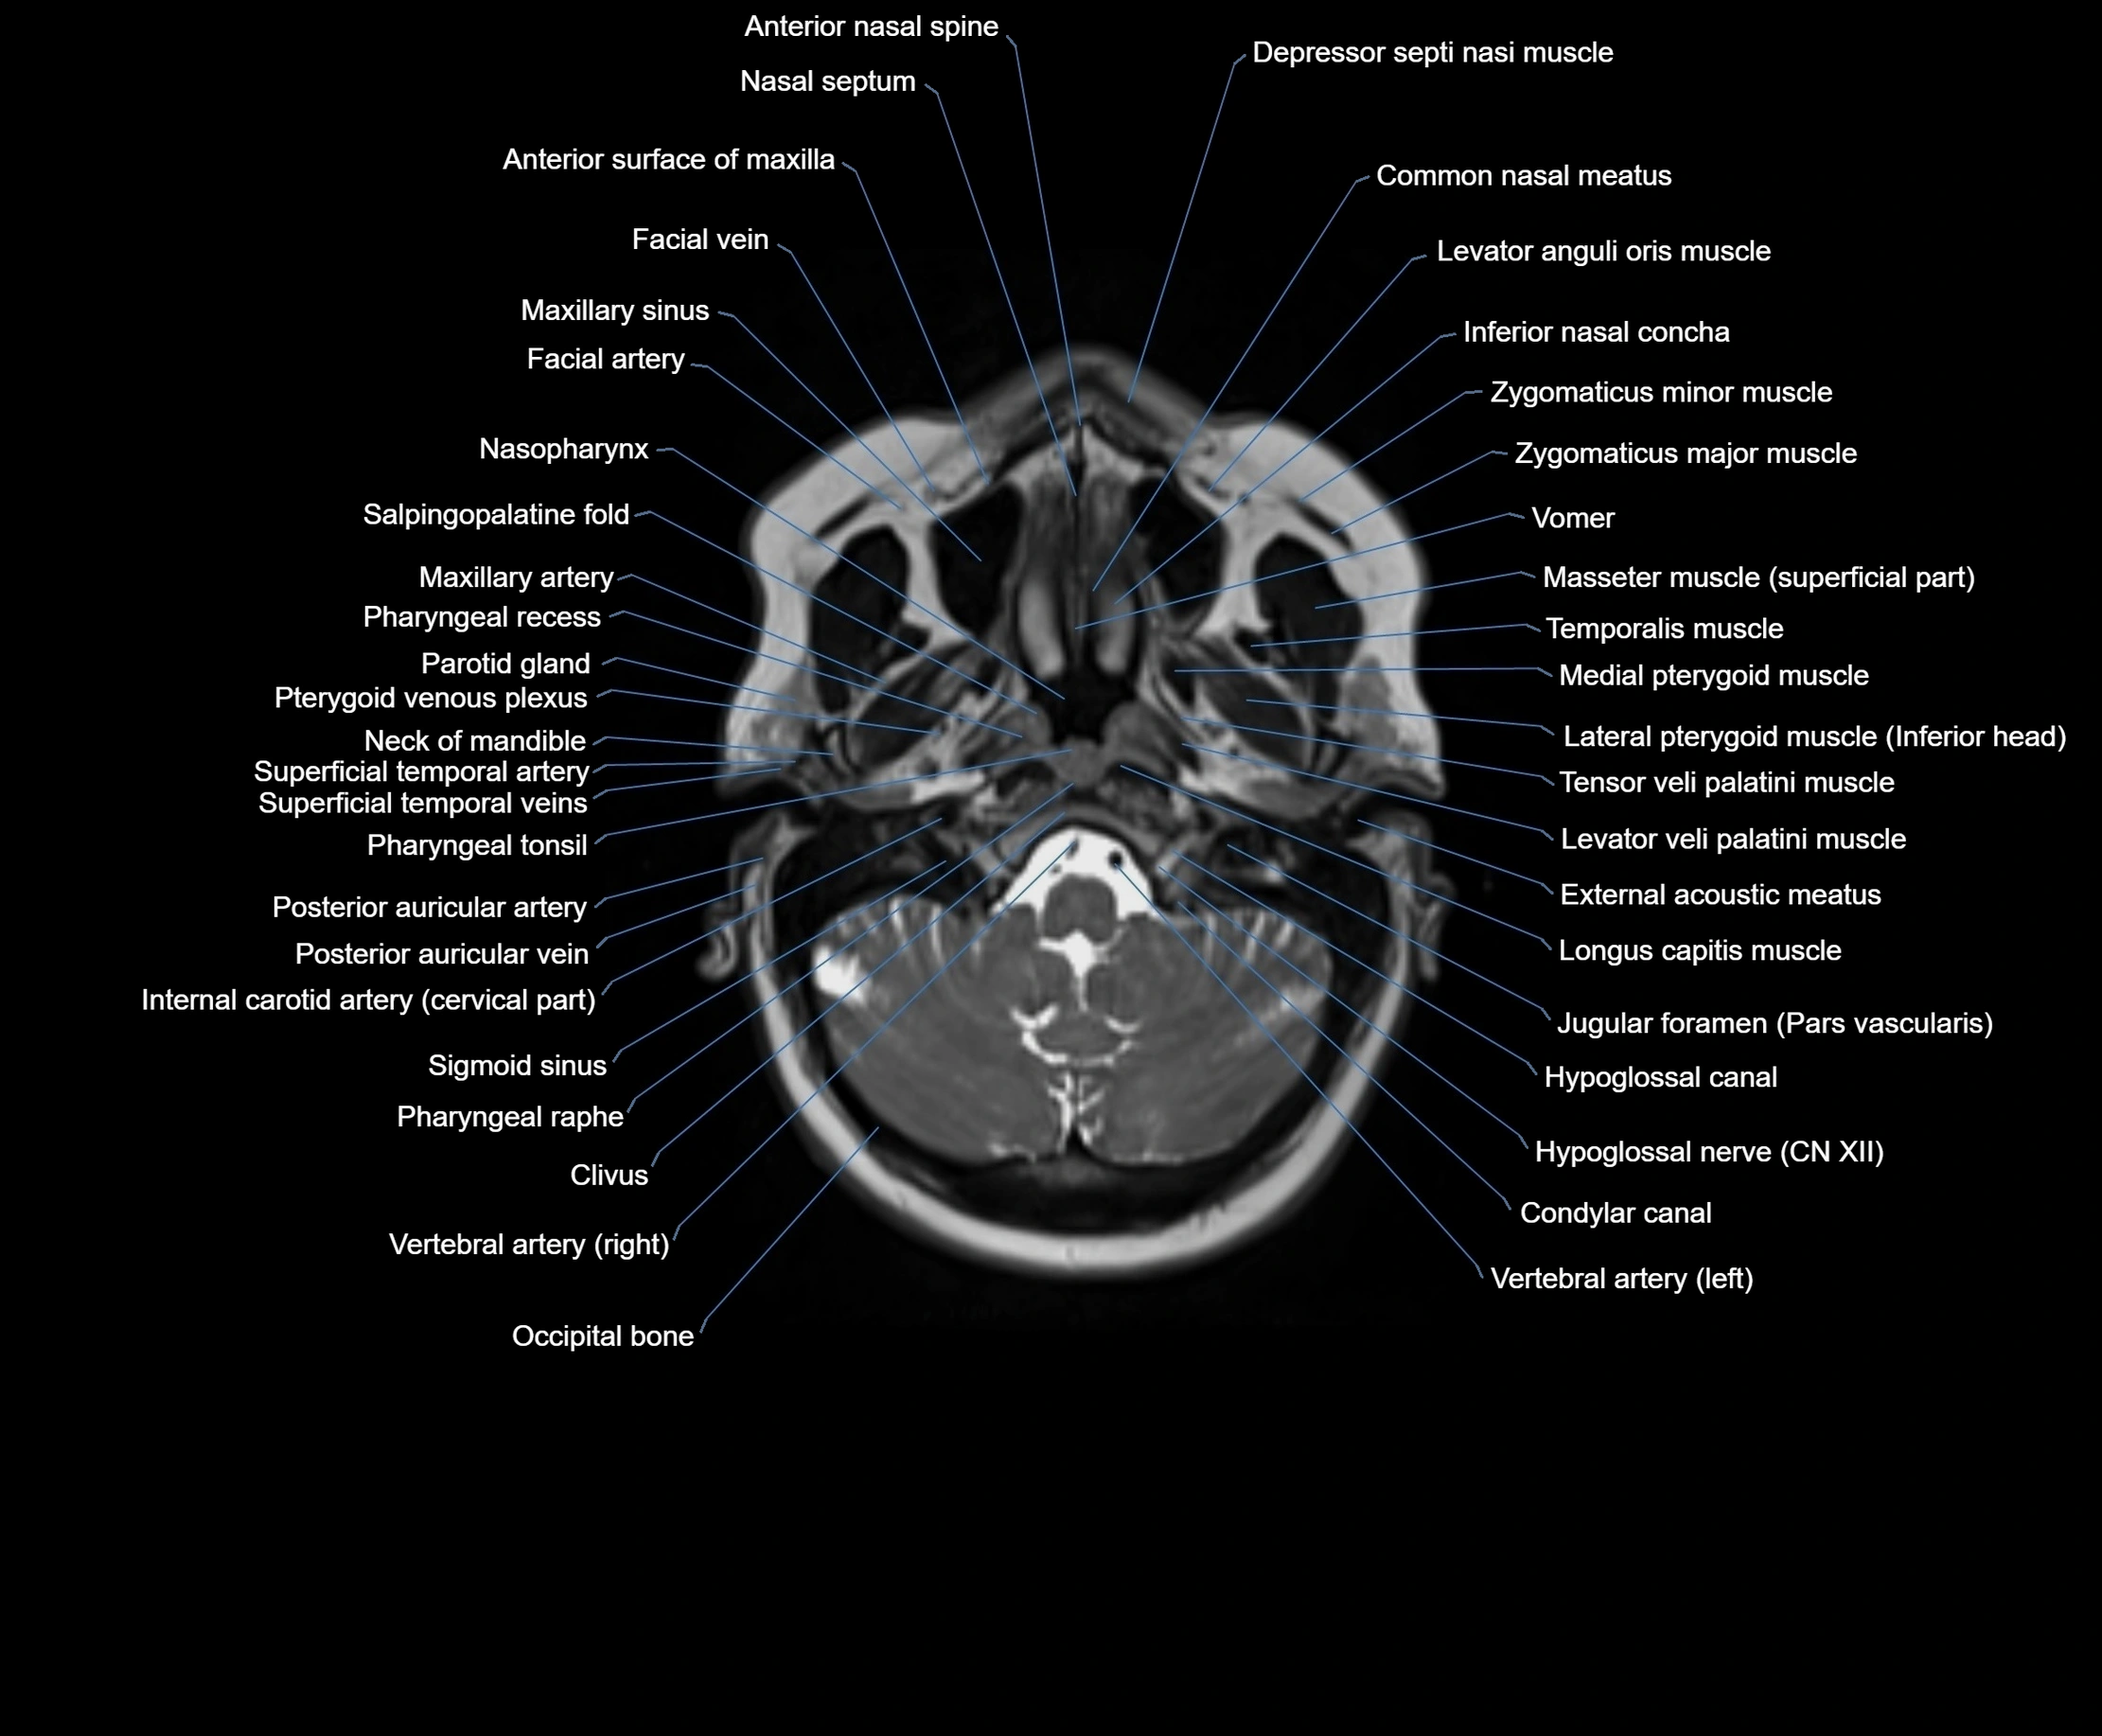

MRI images